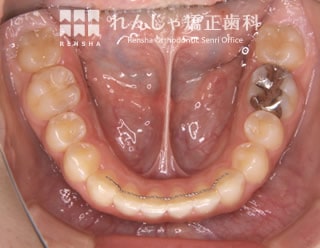

埋伏(15歳 治療期間:2年10か月)

上の犬歯が2本とも埋まったままになっていたので、スペースを確保して引っ張り出しました。

浅い位置に埋まっていたため比較的簡単に牽引することができましたが、骨の深い位置に埋まっていると治療の難易度が非常に高くなります。

| 主訴 | 上の犬歯が出てこない |

|---|---|

| 診断名 | Angle Class I 上顎両側犬歯の埋伏を伴う叢生 |

| 初診時年齢 | 15歳5か月 |

| 装置名 | マルチブラケット装置 |

| 抜歯非抜歯 | 非抜歯 |

| 治療期間 | 2年10か月 |

| 費用の目安 | 約89万円+消費税(検査料金、都度の処置費用等も合わせた総額) |

| リスク副作用 | 歯の移動に伴う軽微な歯根吸収、歯槽骨吸収、歯肉退縮(いずれも本症例ではほぼ無し)、矯正器具装着中のカリエスリスク増大(本症例ではカリエス発生無し) |